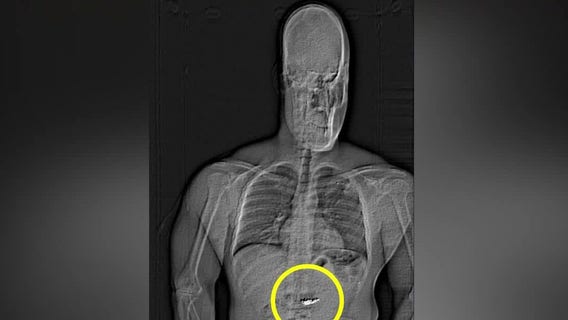

Man accused of swallowing luxury earrings

Larry Lawton, a crime prevention specialist, joins FOX 35 to talk about Jaythan Gilder, who was recently arrested for allegedly stealing $769,500 worth of jewelry from Tiffany & Co. at the Mall at Millenia. Authorities say Gilder, who has a history of similar crimes, attempted to swallow the stolen earrings during his arrest and now faces charges of robbery with a mask and first-degree grand theft.